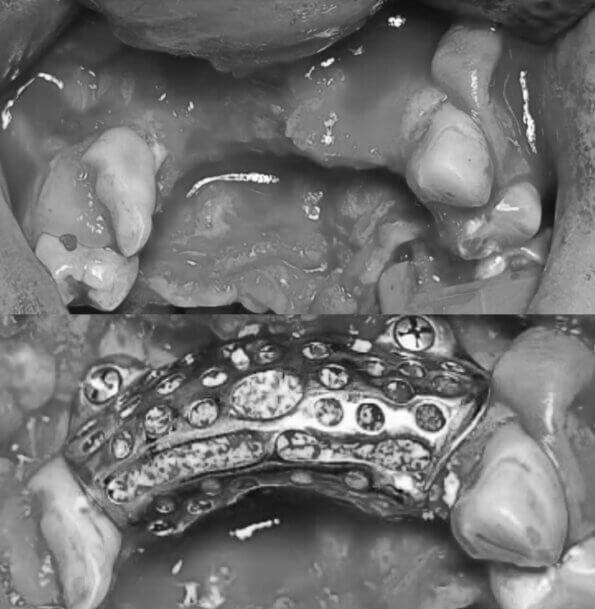

- Ivan is 23 years old and originally wanted to become an engineer. But in 2022, he volunteered to defend Ukraine. A mine explosion destroyed parts of his face. Surgeons were able to reconstruct his upper jaw using a 3D implant.